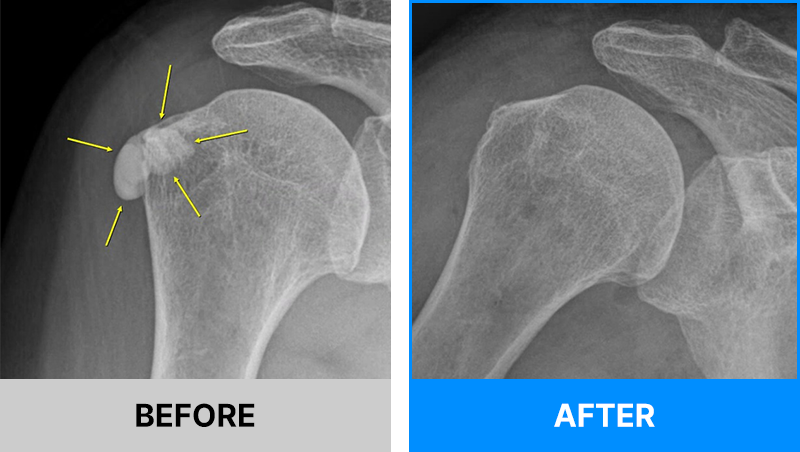

어깨의 석회는 그 시기에 따라 액체형과 고체형 그리고 혼합형으로 존재할 수 있습니다.

액체형 석회를 흡인하는 것은 어디에서나 가능합니다. 하지만 고체형 그리고 혼합형 제거에는 많은 노하우가 필요합니다.

서울거탑정형외과에서는 고체형 석회를 잘게 분쇄하여 뽑아내는 독자적인 기술과 노하우를 보유하고 있습니다.

형성기/휴지기의 고체형 석회

흡수기의 액체형 석회

해당 시술은 석회의 위치를 초음파로 정확히 확인한 뒤,정교한 기술로 진행되는 비수술 치료입니다.

그만큼 의료진의 숙련도와 경험이 매우 중요하므로, 풍부한 시술 경험을 가진 정형외과 전문의를 통해 치료받는 것이 좋습니다.

서울거탑정형외과에서는 풍부한 노하우로 초음파를 통해 정확히 석회를 확인 후 고체형일지라도 미세하게 분쇄하여 제거가 가능합니다.

95%이상 석회 제거가 가능합니다.